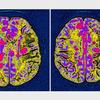

Multipla skleroza je bolezen, pri kateri človekov imunski sistem napade centralni živčni sistem. Prizadeti so možgani, hrbtenjača in očesni živci.